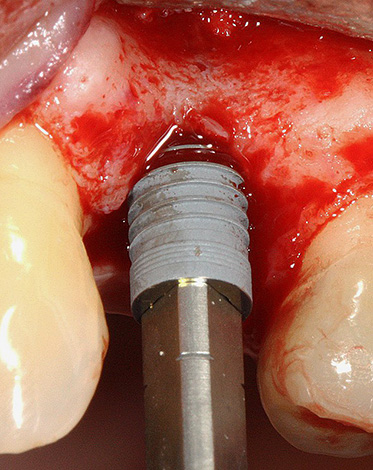

L'operazione per installare l'impianto stesso non richiede più di un'ora e viene eseguita come segue: la gomma viene tagliata, il suo piccolo lembo viene rimosso, il che consente l'accesso al tessuto osseo. Con l'aiuto di frese e frese speciali, si forma un buco nell'osso - il letto sotto l'impianto. Quindi l'impianto viene avvitato nell'osso (come una vite autofilettante) e chiuso con un tappo. Il lembo gengivale ritorna al suo posto ed è suturato - vengono applicate suture.

Il primo metodo di impianto rapido è l'impianto simultaneo. Viene eseguito contemporaneamente all'estrazione del dente (mentre l'approccio classico implica un lungo recupero e guarigione dell'osso dopo tale procedura). Con una tecnica a uno stadio, l'impianto viene installato in un nuovo foro (sfortunatamente, questo non è sempre possibile, soprattutto sullo sfondo dei processi infiammatori, quando il dente deve essere rimosso urgentemente). Con questo approccio, il processo di trattamento è ridotto di uno stadio, il che significa risparmiare tempo e denaro.